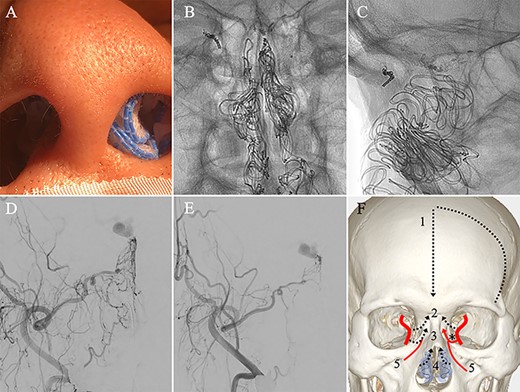

A patient in their 70s with extracranial lymphoma was incidentally found to have ACF–dAVF via head computed tomography and magnetic resonance angiography. Digital subtraction angiography (DSA) confirmed ACF–dAVF with multiple feeding branches, arising from bilateral OphAs, distal IMAs and the left middle meningeal artery (MMA), with cortical venous reflex (Borden type III, Cognard type IV) (Fig. 1). At the patient’s request, we chose endovascular, rather than surgical, treatment. We injected a 20% N-butyl-2-cyanoacrylate (NBCA)–lipiodol mixture into the fistula through bilateral ethmoidal arteries and the left MMA after we placed coils at the terminal branch of the right OphA. However, we could not achieve full penetration into the fistulous connections because of pressure secondary to high flow from the IMA branches, which resulted in incomplete obliteration (Fig. 1). Four months later, we repeated TAE by temporarily reducing nasal blood flow by inserting gauze infiltrated with xylocaine and epinephrine into the nasal cavities. After introducing the guiding catheter, an endonasal surgeon inserted X-ray-detectable surgical gauze infiltrated with 1% xylocaine and epinephrine (1:10 000) into bilateral nasal cavities using a nasal speculum, while paying full attention to avoid damage to the nasal mucosa. Then, we confirmed that the gauzes were placed in appropriate locations in the upper nasal cavity under fluoroscopic guidance. Immediately after insertion, we were able to confirm decreased blood flow from the IMA using DSA (Fig. 2). After this procedure, we navigated a DeFrictor Nano Catheter (Medico’s Hirata, Osaka, Japan) into the terminal branch of the OphA, which was connected to the dorsal nasal artery. Even though there was still a distance from the tip of the microcatheter to the shunt pouch, the NBCA reached the shunt point and penetrated the venous portion (Fig. 3). Follow-up DSA demonstrated complete obliteration of the ACF–dAVF, and blood flow in the nasal mucosa from the IMA branches recovered normally (Fig. 4).

(A) Inserting gauze infiltrated with epinephrine into bilateral nasal cavities. (B and C) Radiograph showing the gauze inserted toward the upper nasal cavity. (D) DSA before inserting the gauze, anteroposterior view, showing blood flow from the right distal IMA. (E) DSA immediately after inserting the surgical gauze, anteroposterior view, showing decreased blood flow from the IMA. (F) Schematic drawing of remaining (red solid line) and occluded feeding arteries (black dotted line) after inserting the surgical gauze. Schema describing that the left dorsal nasal artery (asterisk) remained patent after embolizing the left middle meningeal artery (1), bilateral ethmoid arteries (2) and the right dorsal nasal artery (3), and blood flow from bilateral distal IMAs (4) decreased using our transnasal flow reduction method. (5) Angular artery.